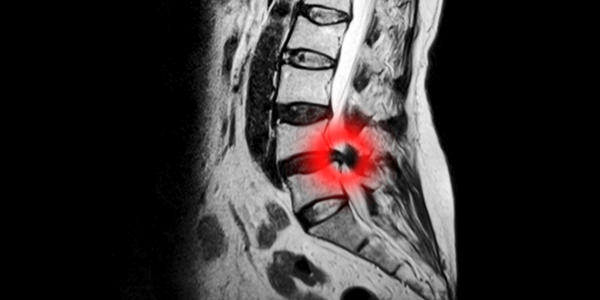

A Herniated/Slipped Disc

The is by far the most common cause of sciatica. Disc herniations can happen slowly over time as a result of wear and tear, or following a trauma such as lifting something heavy.

The disc is a spongy cushion found between the bones in your spine.  During this type of injury it bulges out, pressing on your sciatic nerve and causing pain.